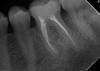

patient2010 Опубликовано 1 февраля, 2010 Автор Поделиться Опубликовано 1 февраля, 2010 взял снимкито что обычная фото сделали после того как удалили пломбу Ссылка на комментарий

Мартовский Опубликовано 1 февраля, 2010 Поделиться Опубликовано 1 февраля, 2010 взял снимкито что обычная фото сделали после того как удалили пломбу Врач был прав - удалять и имплант. Ссылка на комментарий

Андрей Опубликовано 1 февраля, 2010 Поделиться Опубликовано 1 февраля, 2010 взял снимкито что обычная фото сделали после того как удалили пломбу Удалять. Ссылка на комментарий